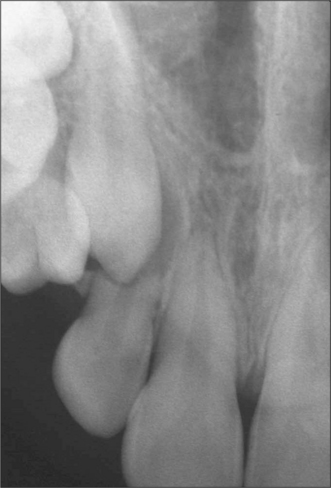

Radiological assessment

The radiographic examination of choice is a panoramic radiograph such as an OPT (Fig. 5.3), although periapical or oblique lateral views of the mandible may be taken as an alternative. When referring a case for treatment all recent relevant radiographs should be included to avoid further exposure to ionizing radiation.

image

Fig. 5.3 A mesioangular impacted lower third molar on the right and distoangular impaction on the left. (Note the unerupted third molars in the maxilla.)